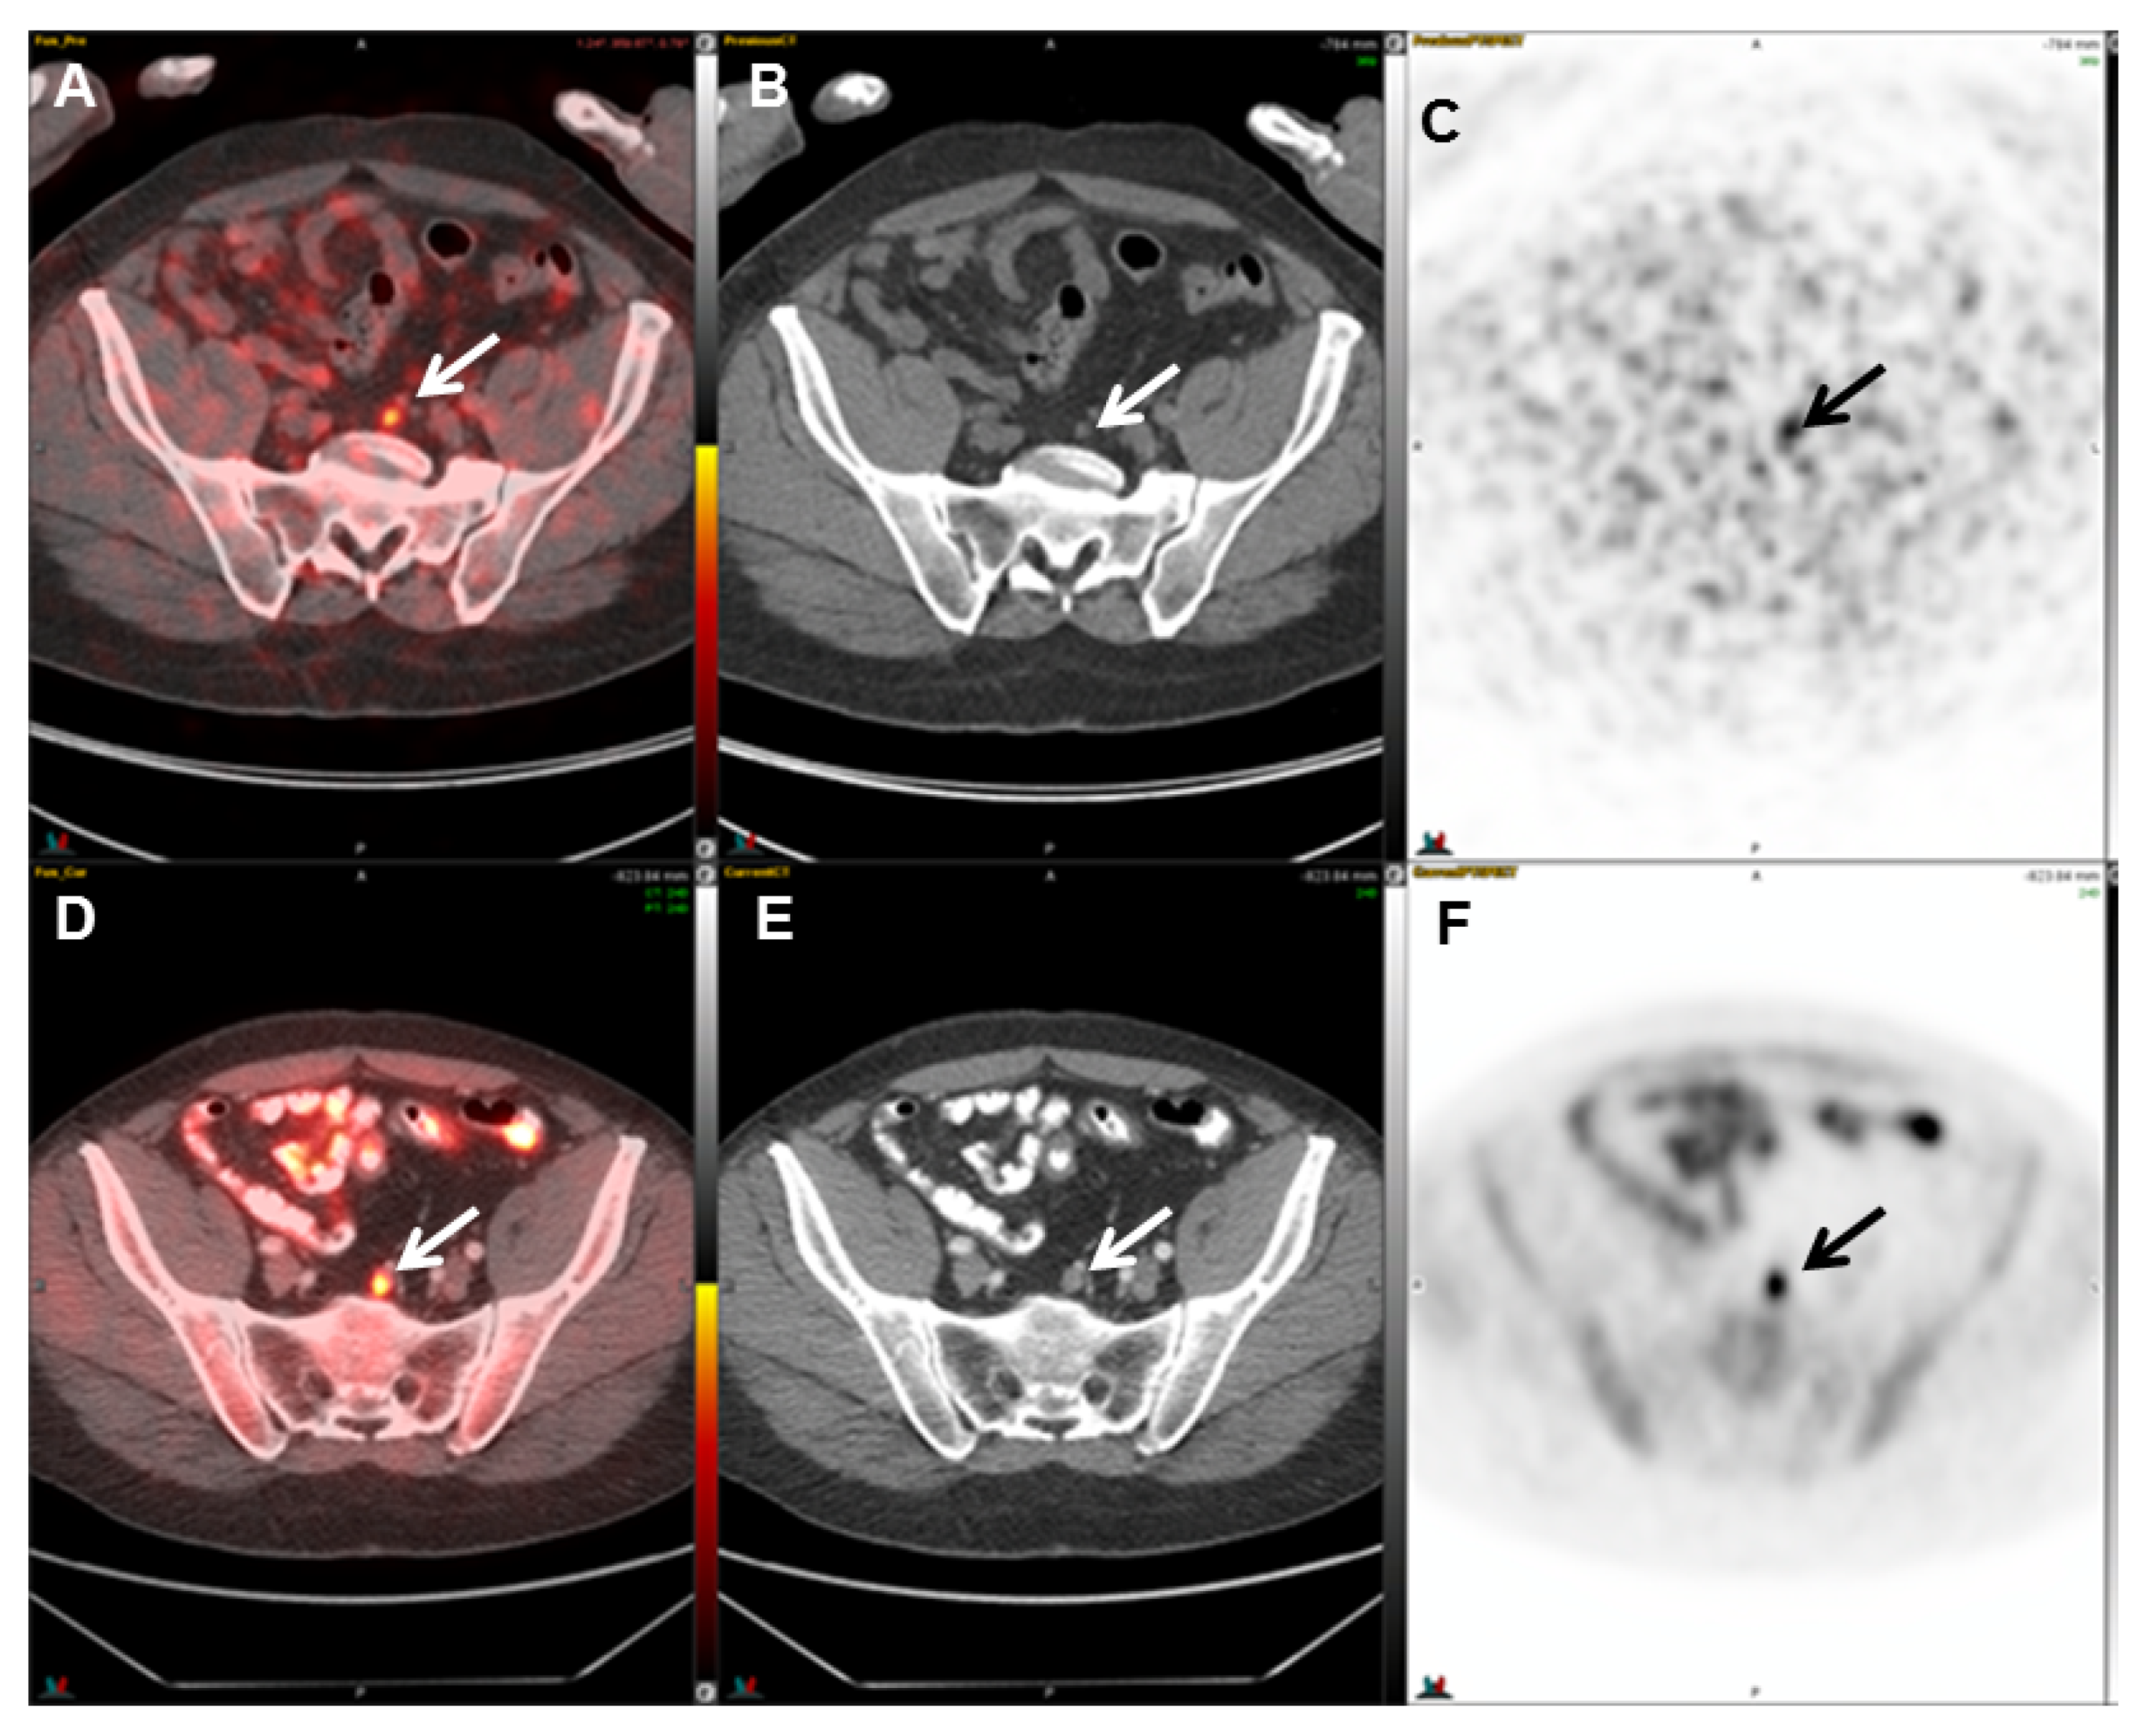

2.4. 18F-Fluciclovine (FACBC) PET